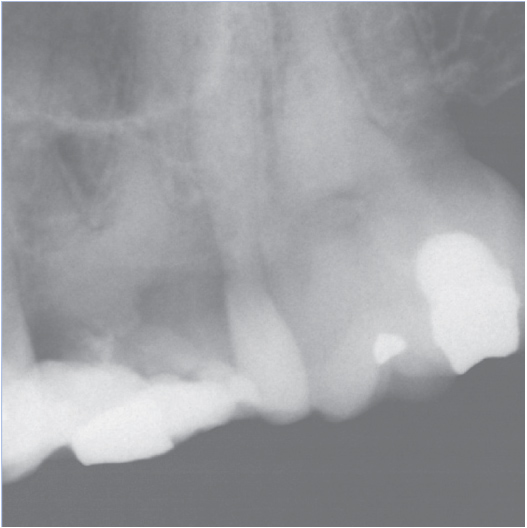

Before

After

Before Root Canal treatment

After Root Canal treatment